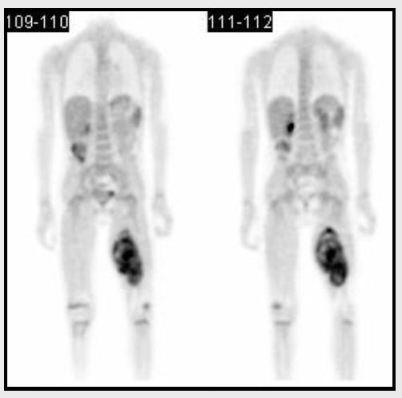

7. pacient

Čtyřletý chlapec s nejasným nálezem na

magnetické rezonanci v oblasti levého stehna. PET/CT zobrazilo

objemné ložisko s metabolismem maligní nádorové tkáně.

8. pacient

Nejmenší pacient vyšetřený na našem oddělení.

Třítýdenní holčička měřící 40cm a vážící pouze 1,6kg. Byla

přivezena z neonatologické kliniky a vyšetřena pro podezření na

zhoubný novotvar měkké tkáně dolní končetiny. PET prokázal zvýšenou

aktivitu v plosce levé nohy.